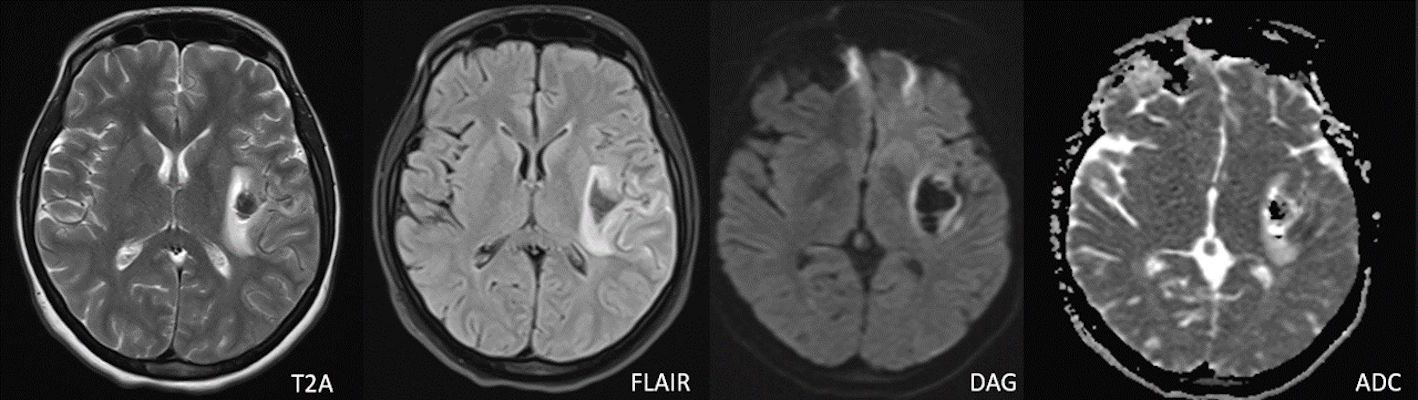

- Difüzyon ağırlıklı görüntülemede (F) difüzyon kısıtlanması izlenmiyor.